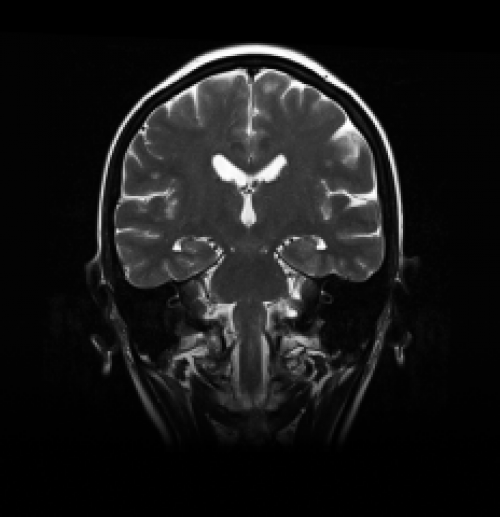

Фронтальная плоскость